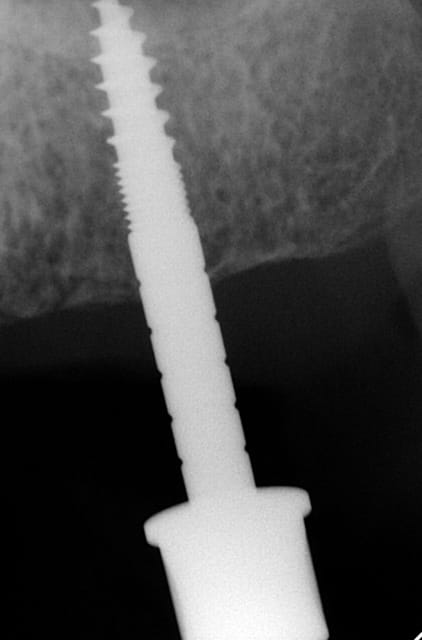

3ème photo: radio d´un patient âgé de 73 ans qui souhaitait avoir des dents fixées.Comme on l´observe il n a plus de place après les foramines mentales.Nous avons donc utilisé juste l´os interforaminal. Nous avons suivi le concept du prof. Nentwig qui consiste à pouvoir ajouter 2 dents dans chaque quadrant dans la mandibule.

Les forets utilisés ont 3 faces et sont coniques (250 trs/min) permettent une condensation de l´os et un traitement minimalement invasif.